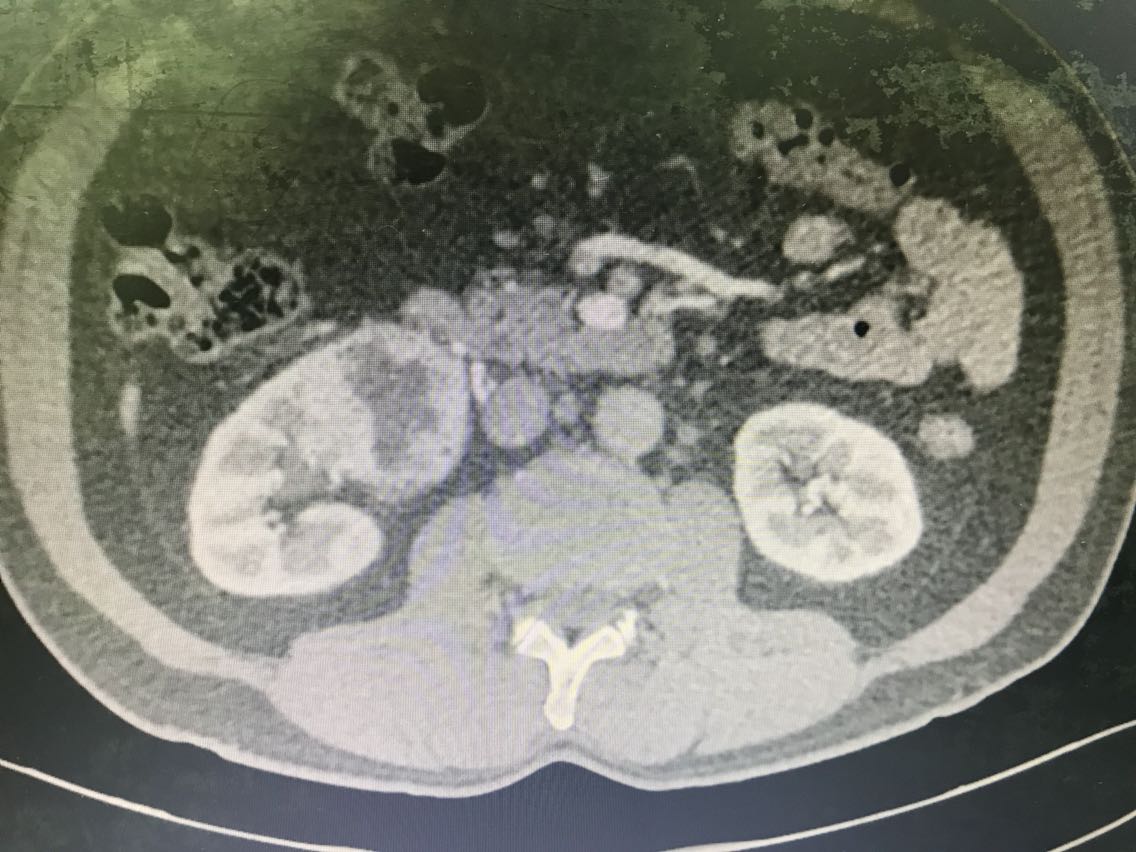

患者男性,62岁。 主诉:咯血、体检发现右肾占位1+月 现病史:1+月前,患者无明显诱因出现反复咯血,为痰中带鲜血,无胃内容物,无畏寒、发热,无胸闷、胸痛,无潮热盗汗,无恶心、呕吐,无腹胀、腹痛等不适。于当地医院就诊,行相关检查(具体报告未见)考虑“支气管扩张”,行相关治疗(具体不详)后患者咯血症状好转出院。患者于住院期间检查发现右肾占位(报告未见),无腰痛、腰胀,无血尿、蛋白尿,无尿少及排尿困难。患者为进一步诊治,于我院门诊就诊,查肝肾功能、肿瘤标志物、小便常规未见明显异常。上腹部增强CT:右肾前下份占位,考虑透明细胞癌(T3aN2Mx),左肾结石、囊肿,腹膜后多发淋巴结,肝脏右后叶下段小囊肿,腹主动脉管壁钙化。现患者为进一步明确诊断及治疗,入住我科。 既往史无特殊。

查体无特殊。 辅助检查: 心电图:窦性心律,电轴左偏,左前分支阻滞,不完全性右束支阻滞。 上腹部增强CT:右肾前下份占位,考虑透明细胞癌(T3aN2Mx),左肾结石、囊肿,腹膜后多发淋巴结,肝脏右后叶下段小囊肿,腹主动脉管壁钙化。

诊断:1、右肾肿物:肿瘤可能性大,其他?;2、支气管扩张。 治疗:腹腔镜根治性右肾切除 术中见右肾前下份可见肾脏肿物,大小约6.1*5。8cm,病变突出右肾轮廓外,未见明显的突破肾周筋膜。与肾周组织、右侧肾静脉、右侧输尿管上段粘连明显。